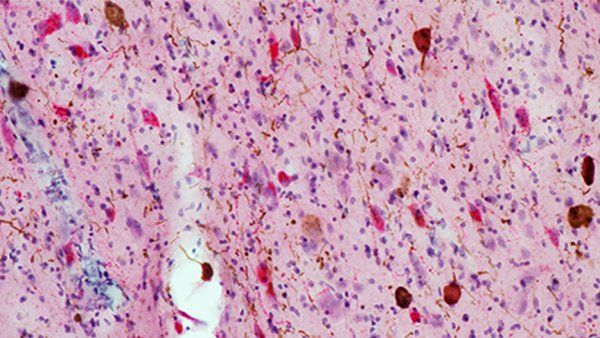

Why Do Some Brain Regions Resist Alzheimer’s?